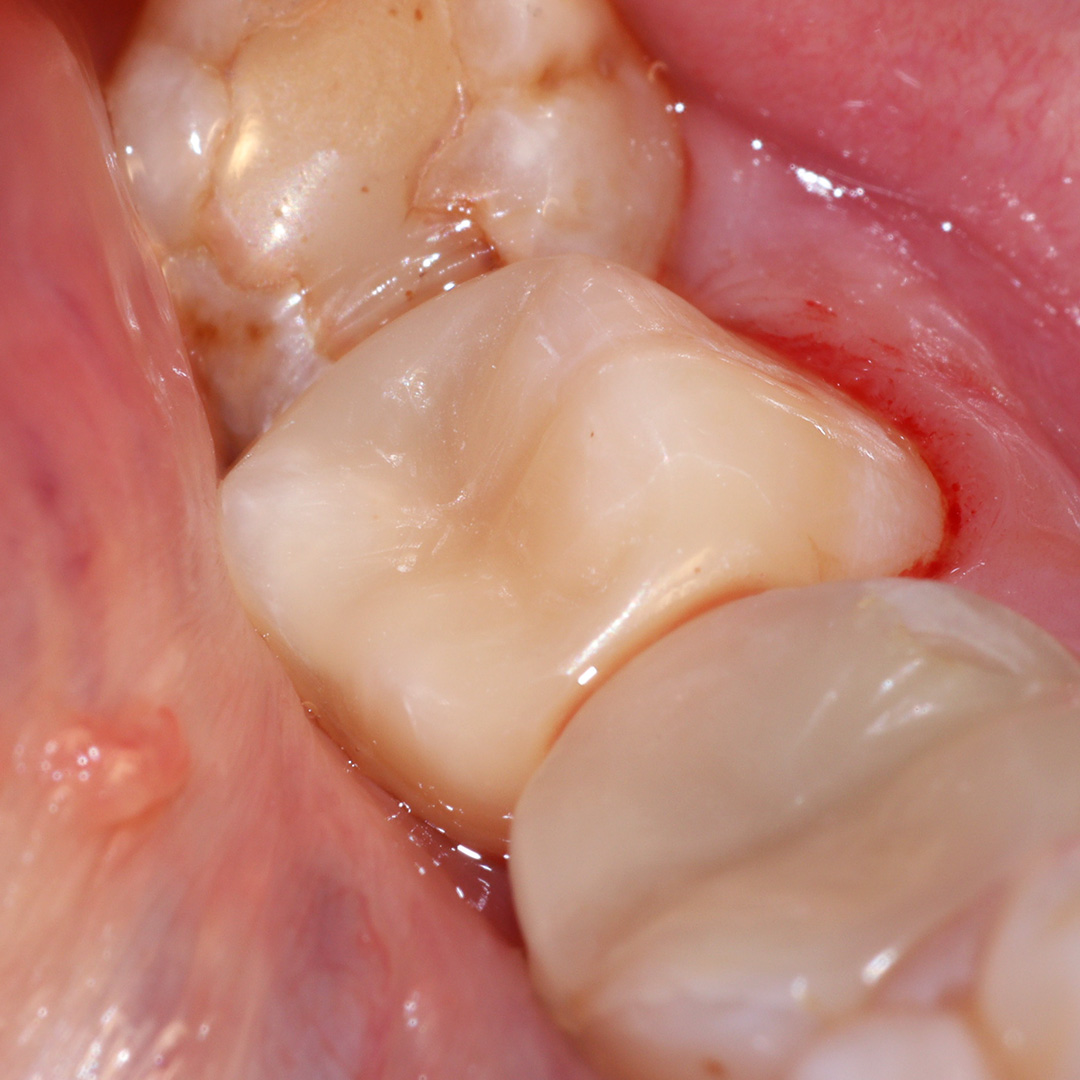

В ходе лечения были проведены следующие мероприятия:

- механическая и медикаментозная обработка кариозной полости;

- пломбирование с применением светоотверждаемого композита Estelite;

- проведено микроконтурирование и макроконтурирование пломбы.